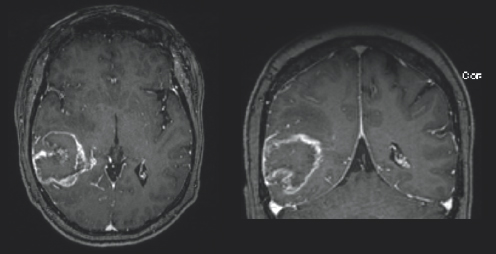

(Left) There is charcoal grey color surrounded by black space and a thin light gray outline. There is a black colored blob in the bottom left side of the image with three white blobs around it; two on the bottom and one on the top. Each white blob is highlighted by white arrows. There is a small light gray circle to slightly to the right of the center of the image. It is circled in white. (Right) There is charcoal grey color surrounded by black space and a thin light gray outline. On the left side of the image, there is a black blob with a white colored blob on top of it. There is a white arrow pointing downward towards the white blob.

FIGURE 3.3 Brain MRI after surgery. Follow-up axial (left) and coronal (right) post-contrast images, obtained 34 months follow-up, show progressive increased size of nodular areas of abnormal enhancement that appear bright after being injected with IV contrast, along the superior and anterolateral margins of the resection cavity (white arrows), with a new abnormal ependymal enhancing nodule in the left frontal horn (white circle), concerning for recurrent tumor.

A month after her surgery, Janet began chemotherapy and radiation treatment. She began trialing different chemotherapy drugs recommended by her team of physicians to pinpoint which would be most effective for her tumor. She was unable to be treated with the standard-of-care drug, TMZ, due to a severe anaphylactic allergic reaction. Despite desensitization to try to ween her on TMZ use, she continued treatment with lomustine, a different chemotherapy drug. Janet was placed on multiple clinical trials starting with the Belinostat/MRSI (magnetic resonance spectroscopic imaging) study and later the 5-ALA (5-aminolevulinic acid) study. Early on in her treatment, Janet turned to tumor treating fields (TTFs), to see if that form of treatment could provide her the benefit of tumor reduction. TTFs are commonly used in the form of an Optune® device. An Optune® device is a physical, white-colored cap that patients can place over their shaved heads to reduce cancer cell growth through the electric fields that the device omits. In the fall of 2019, Janet moved her care from Emory University Hospital and Wake Forest Hospital to the University of Cincinnati Medical Center to follow her neuro-oncologist, Dr. Soma Sengupta, with whom she had formed a close relationship. Due to the progression of her disease Janet underwent a re-resection surgery in March of 2020 and was placed on the adjuvant letrozole drug study. She then started the chemotherapy drug bevacizumab and required stereotactic radiosurgery (SRS) for a new lesion (Fig. 3.2–3.4). She continued care through her doctors in Cincinnati in conjunction with the care she was receiving at Wake Forest Hospital. She felt prepared but nervous each time she underwent imaging because she knew if her tumor had grown, it would result in a change of course to her treatment.